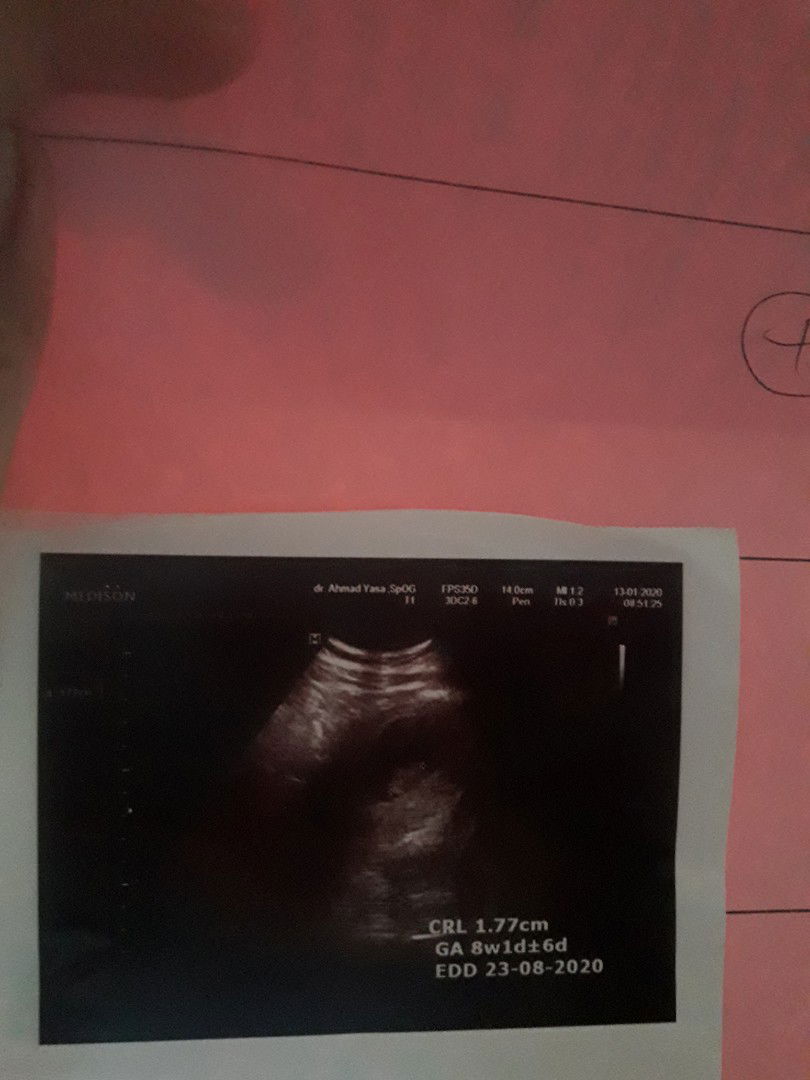

usg 6 minggu

Normal ga uk 6 week